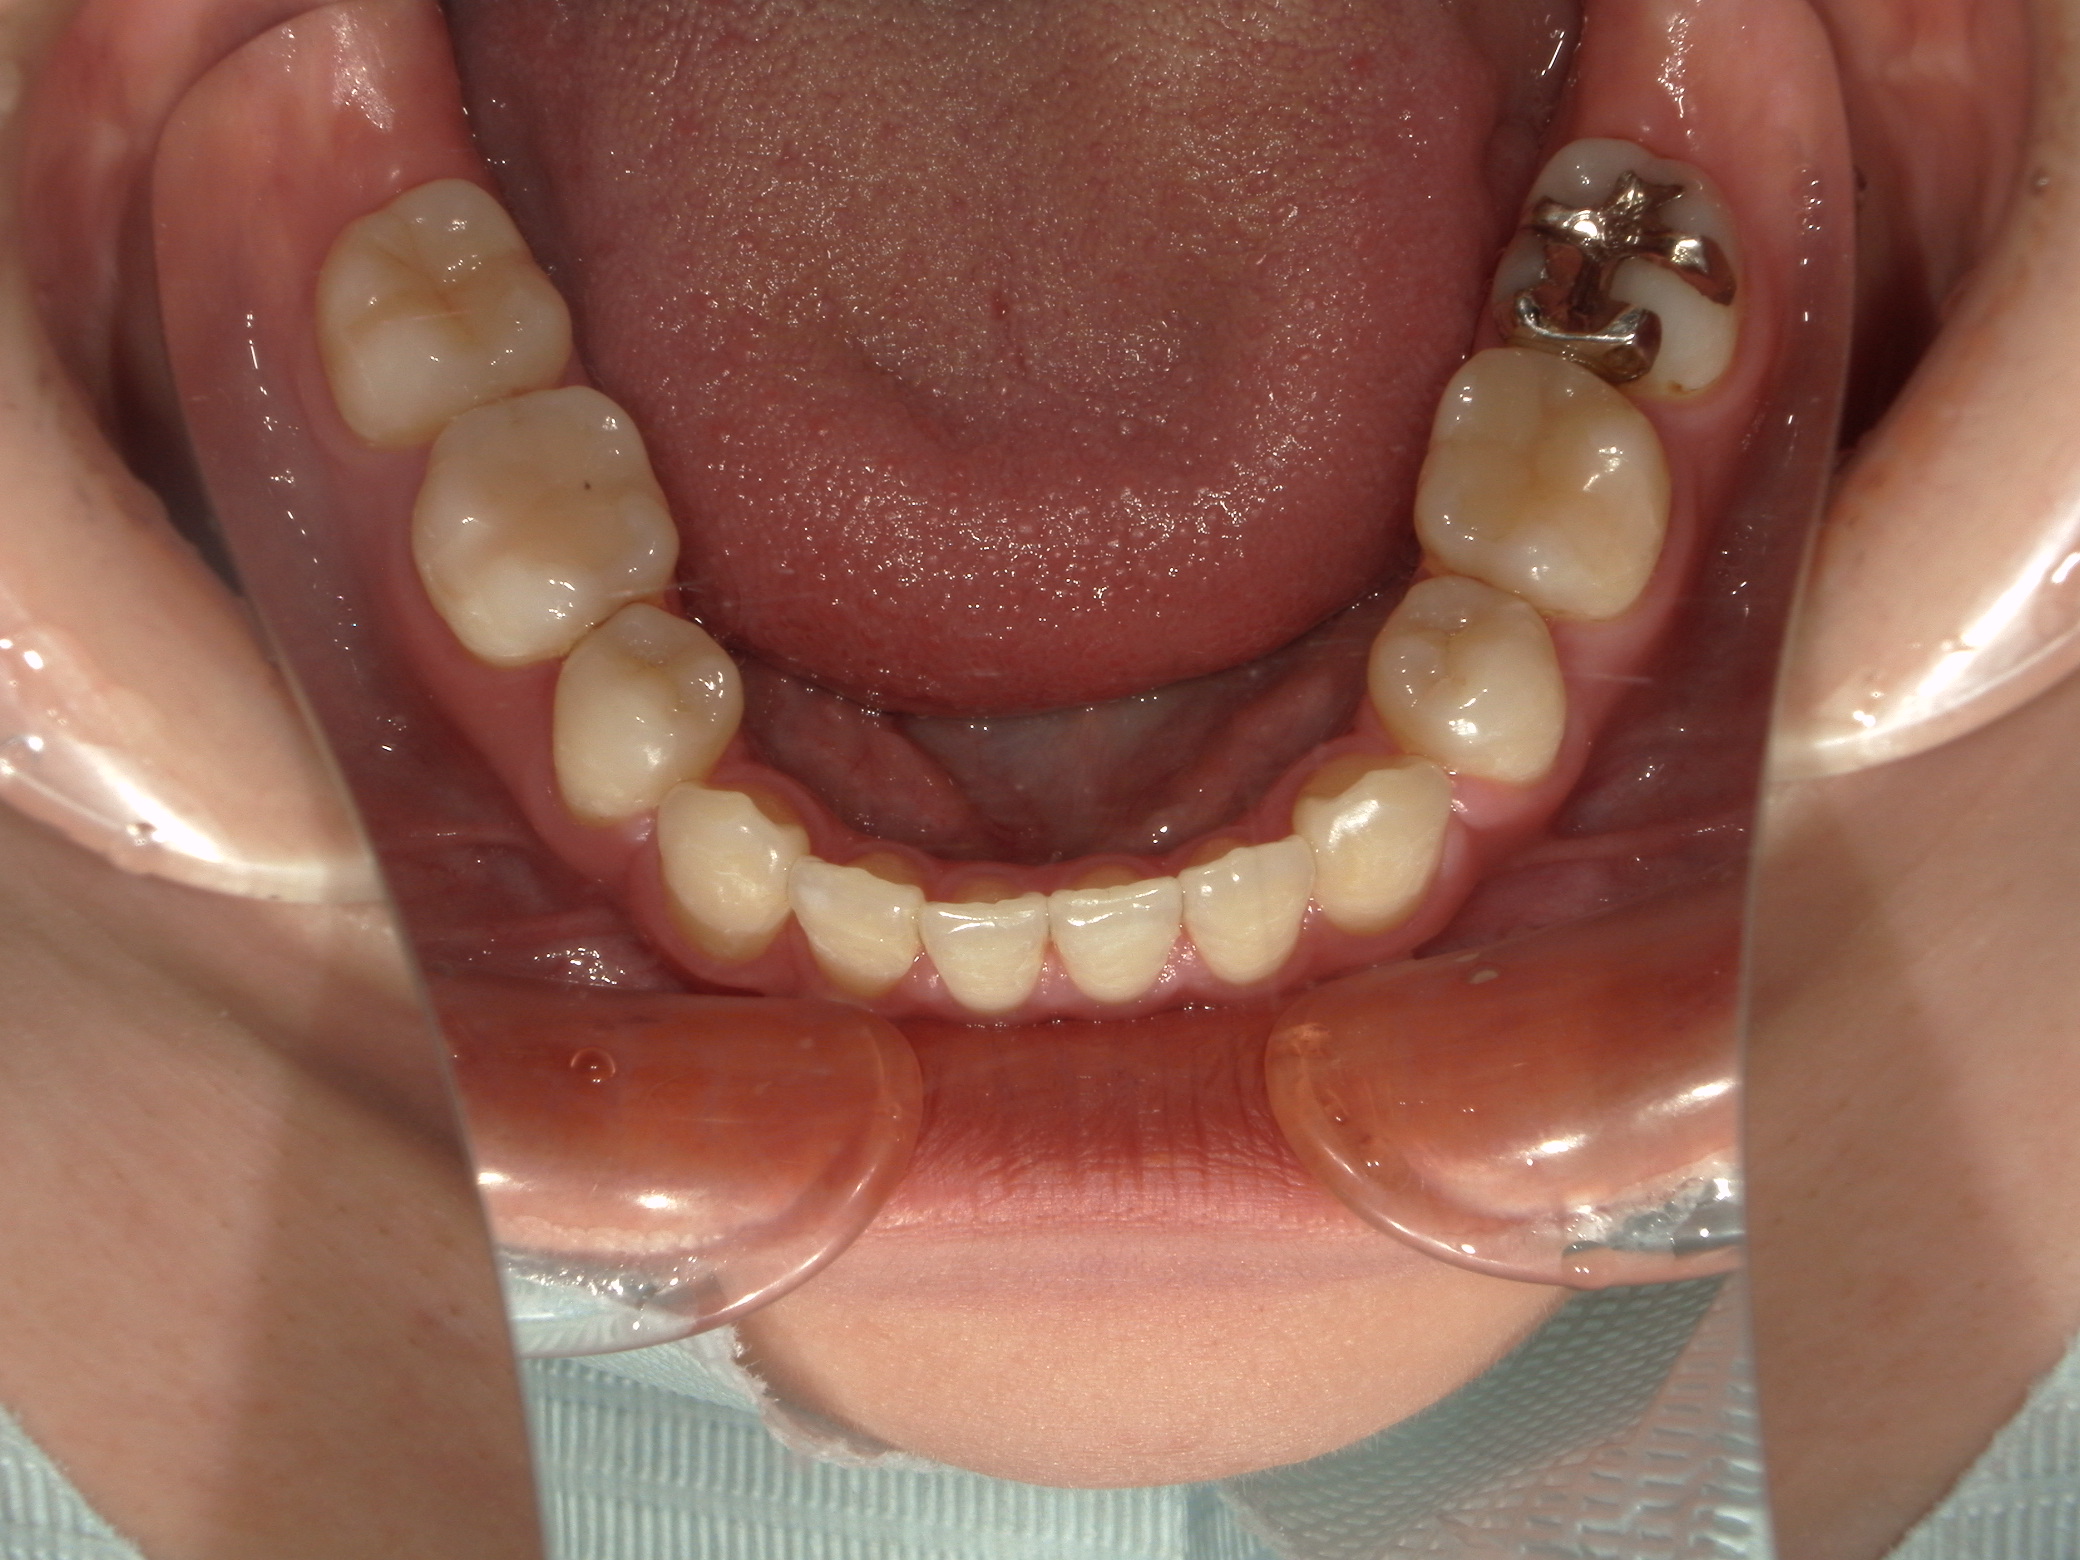

口元の突出を主訴に来院。

上下小臼歯抜歯により突出感を改善する計画を立てた。確立した咬合を崩さないように治療を進める事を目標とした。

患者はハーフリンガル矯正を希望した。

治療後、口元の突出感の改善、咬合関係は維持することができた。